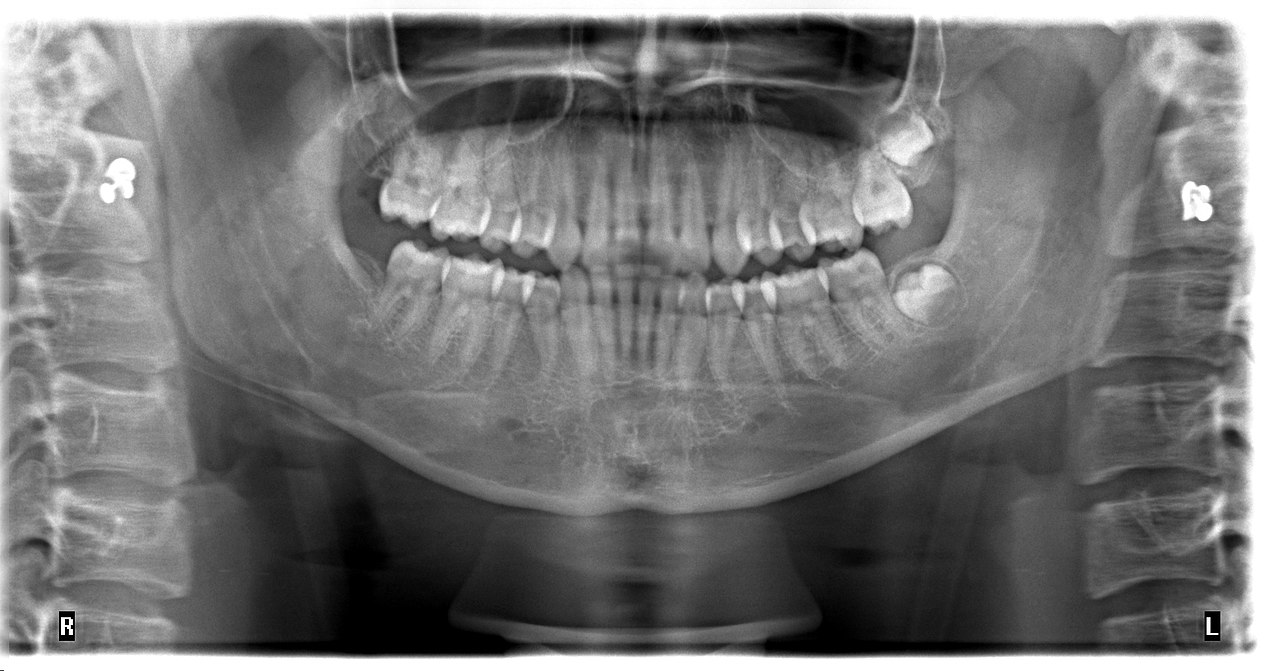

Toregem Biopharma, a biopharmaceutical start-up funded by Kyoko University, is developing a drug that could help people with congenital or acquired tooth loss.

The pathway to developing the drug started in 2007 when their team of scientists discovered that a deficiency in the USAG-1 gene led to the development of additional teeth in mice. The team hypothesised that inactivating the USAG-1 protein with a drug may regenerate teeth in humans with congenital and/or acquired tooth defects.

The drug is now entering human clinical trials, this year in healthy adults to assess safety, and the following year in children between 2 and 6 years old who are born without some or all permanent teeth. If these trials are successful, the drug may undergo regulatory approval for use in dentistry surgeries worldwide.